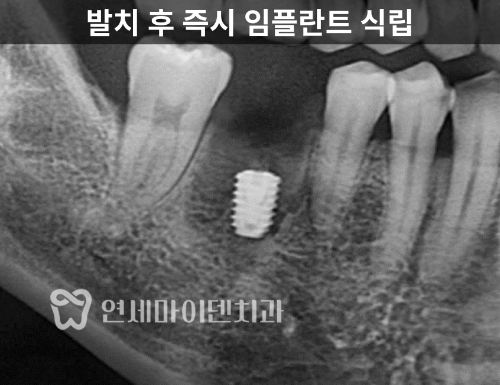

치료 기간 단축을 위한 '발치 즉시 임플란트'

문제는 시간이었습니다.

두 달 이내에 임플란트 식립 후

보철까지 완성하기는 현실적으로 어려웠습니다.

그래서 이번 귀국 기간엔

발치 후 즉시 임플란트 픽스쳐까지

심는 과정만 진행했고,

2차 및 최종 보철은

다음 귀국 때 연결하기로 했습니다.

이번 케이스는 뼈 상태가 비교적 양호했고,

발치 중에 셉탈본(치아 뿌리 사이의 뼈)가

최소한으로 손상되었습니다.

따라서 고정력 30n을 확보할 수 있었고,

발치 후 즉시 픽스쳐 식립이 가능했습니다.

임플란트 픽스쳐를 정확한 위치에 심고,

뼈 이식과 멤브레인으로 봉합까지 마무리했습니다.

이후 실밥 제거 후 출국하셨고,

보철은 다음 귀국인 6개월 뒤에 진행되었습니다.